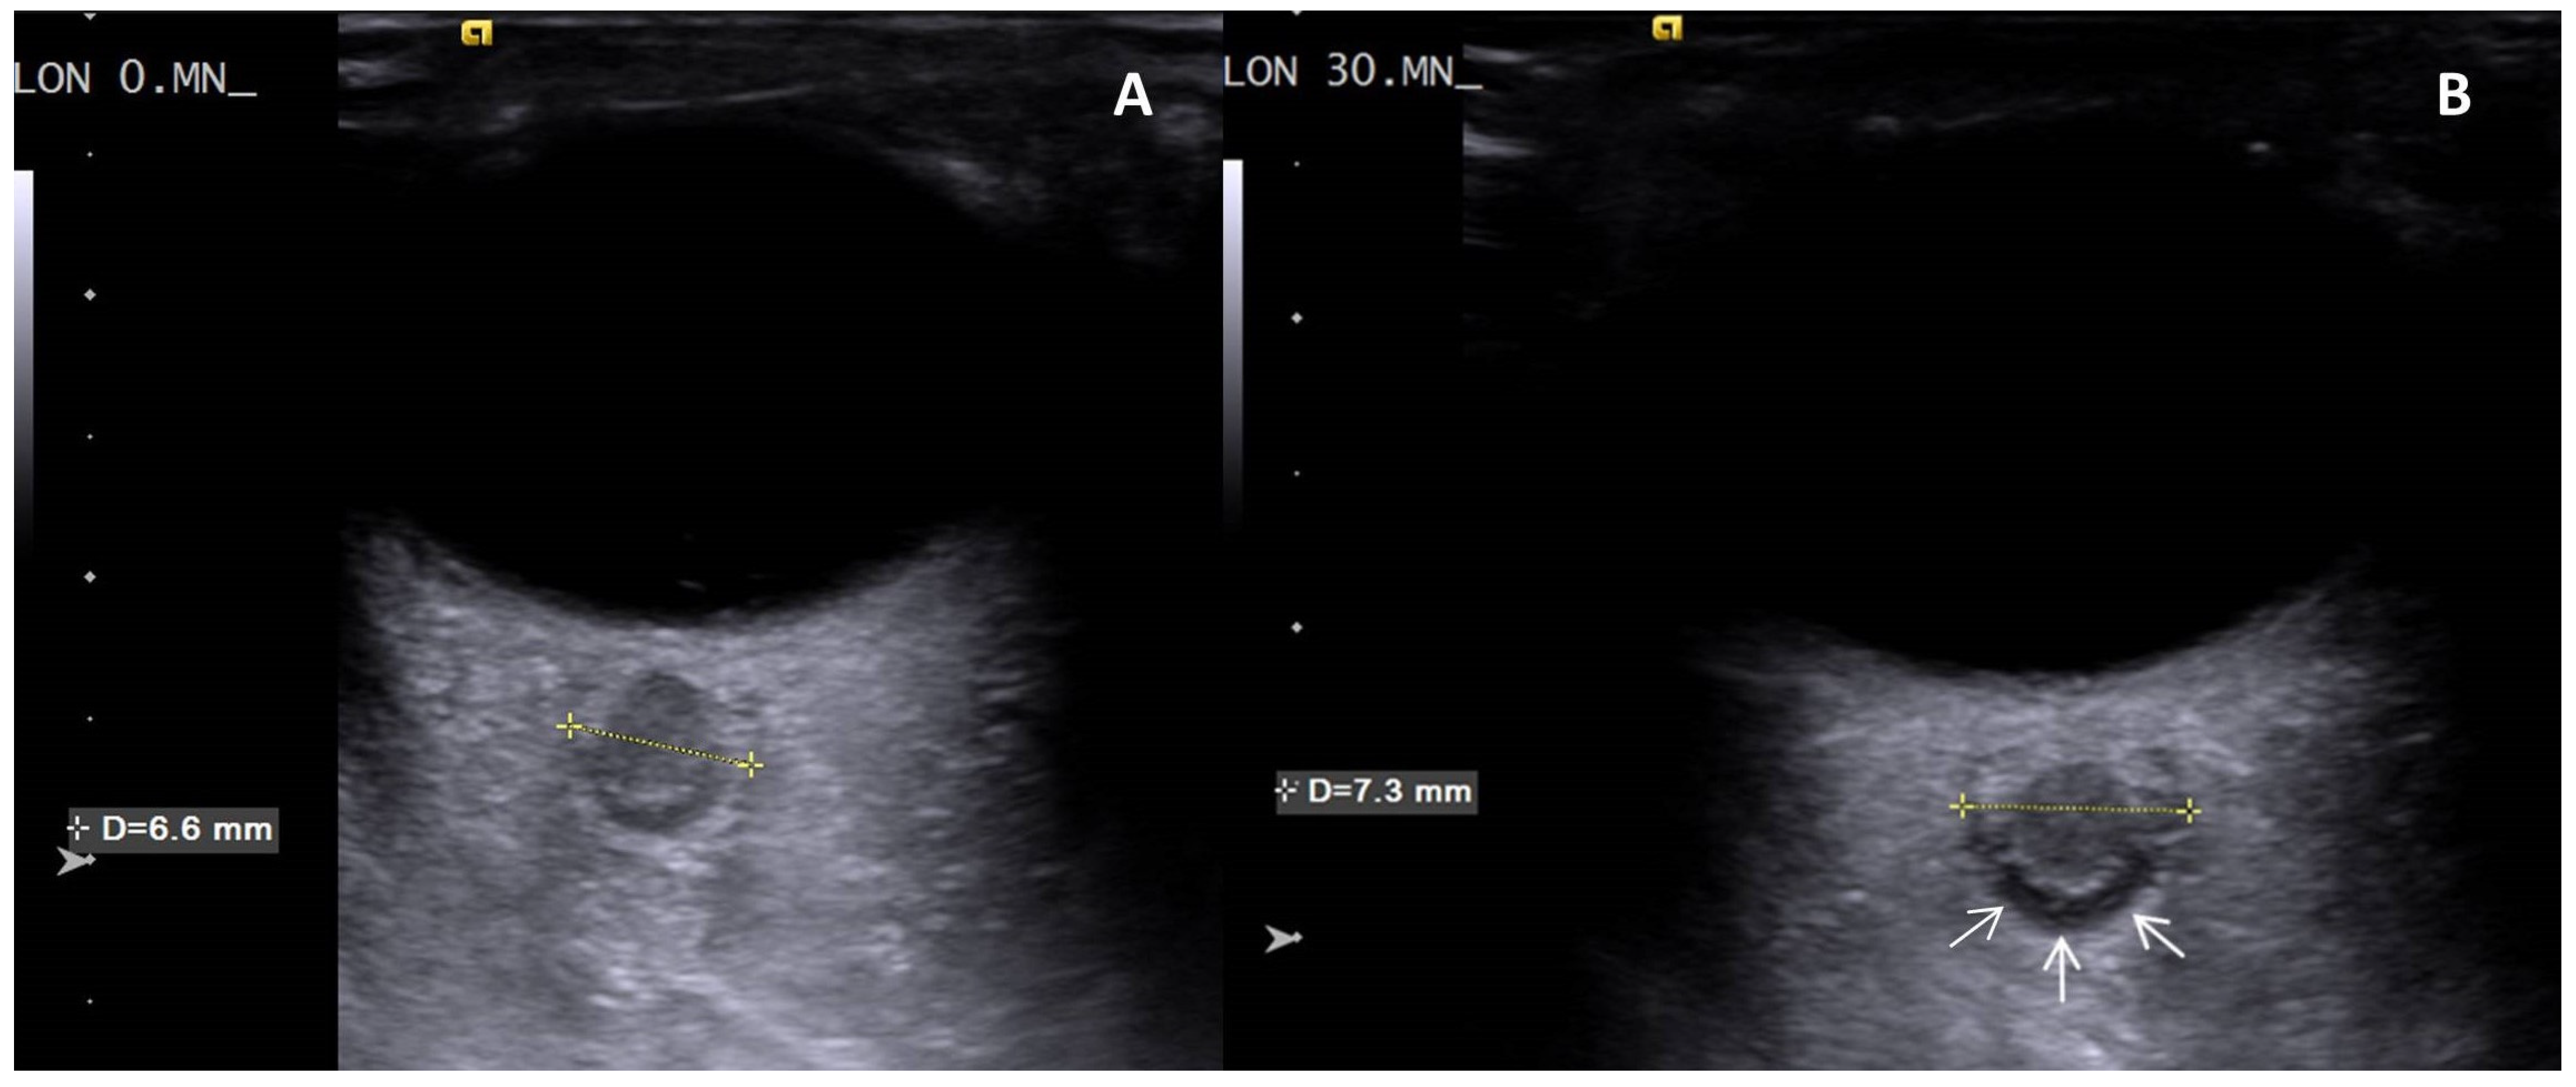

A significant increase was found when T30 values were compared to the basal values for the right and left ONSD (p < 0.001, p < 0.001, respectively) (Table 4, Figure 2, Supplementary Materials Figure S5).

In addition to changes in cerebral oximetry, the increase in ONSD further supports the finding of acute cerebral congestion. The optic nerve, an extension of the brain, is encased by the meninges and links the cerebrospinal fluid of the optic nerve sheath (ONS) directly with that of the subarachnoid space. It is known that an increase in intracranial pressure (ICP) results in an increase in fluid in the ONS, leading to an increase in ONSD. Ultrasonographic measurement of ONSD allows indirect assessment of ICP increase with sensitivity and specificity of 75–100% and 100%, respectively [31,32,33,34,35,36,37,38,39]. Consequently, while cervical hyperextension had minor impact on cerebral arterial blood flow in our study, it significantly hindered venous drainage, resulting in acute cerebral congestion. Our study’s key findings showed a significant increase in ONSD bilaterally due to elevated ICP in the acute cerebral congestion clinic (Figure 2). In a study by Lim et al., ONSD increased significantly after CO2 neck insufflation and decreased after deflation in robot-assisted thyroidectomies. They explained this by addressing the reduction in jugular venous blood flow due to higher pressure in the neck; however, they overlooked the effect of cervical hyperextension. Notably, ONSD remained above baseline until just before PACU discharge, although this was not statistically significant [24]. This finding and discussion are similar to the acute cerebral congestion observed in our study.

Figure 2. Transorbital ultrasound visualization of the axial plane of the left eye. The optic nerve appears hypoechoic and is surrounded by the hyperechoic optic nerve sheath. (A) Optic nerve sheath in a volunteer with normal intracranial pressure at T0 showing no visible subarachnoid space around the optic nerve. (B) Optic nerve sheath in the same volunteer at the 30th minute of cervical hyperextension position demonstrates a significant subarachnoid space around the optic nerve (white arrows), indicating elevated intracranial pressure.